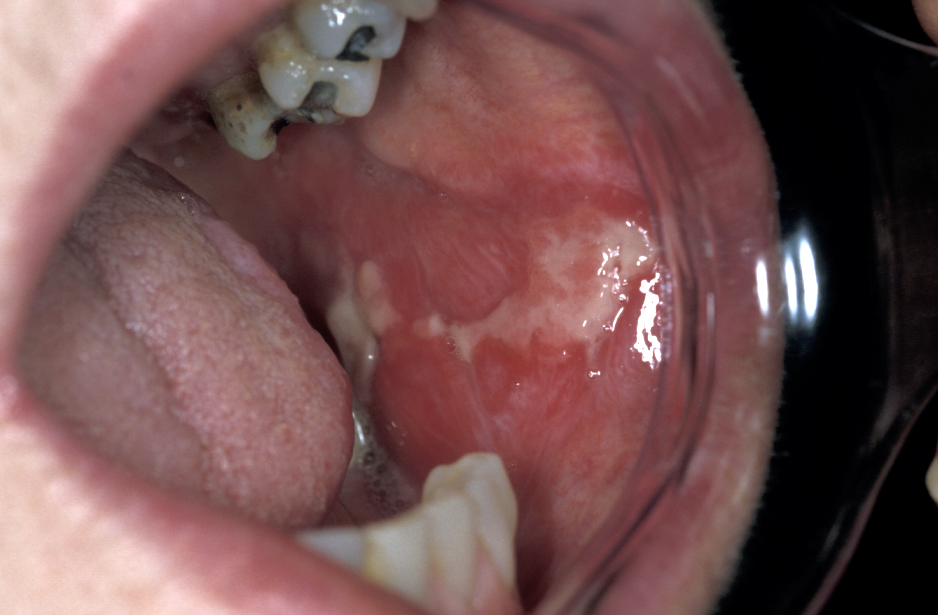

Oral lichen planus, the mucosal variant of a common skin condition, is a chronic condition and requires long-term management. Oral lichen planus can be asymptomatic or a rather debilitating condition with a severe symptom burden, especially erosive and ulcerative forms of the condition (Figure 3). The term oral lichen planus covers a range of similar conditions. The potential of oral lichen planus for malignant transformation remains a matter of debate. It has been estimated that there may be a 1 to 3 % risk for malignant transformation.

The chronic nature of the condition, combined with diagnostic difficulties, a potentially significant morbidity (in particular pain) and an insufficient understanding of the cause(s) all contribute to the need for patience on behalf of all involved. This situation also accounts for the fact that there is no widely agreed therapeutic approach for the management of this group of conditions.

The topical application of a number of different steroids remains the first-line medication scheme. This could be in the form of sublesional injections, but some patches drenched with a slow-release form of clobetasol (a corticosteroid) are also being tested. Failure of the lesions to resolve under topical treatment with steroids is not uncommon. In such cases, topical application of a different type of agent, a calcineurin inhibitor (immunomodulating agents that reduce inflammation) such as tacrolimus or pimecrolimus may offer an alternative.

For persistent cases that do not resolve under topical treatment schemes, systemic steroid therapy may be necessary. Other treatment schemes favour the use of low-intensity laser therapy, LILT rather than pharmacological drugs. Some studies have demonstrated that LILT helps with pain management, can reduce the clinical signs of oral lichen plans, is similarly effective as more established drug treatments and avoids the adverse effects of, for example, systemic steroids. It remains to be seen if these initial findings about LILT can be confirmed in larger systematic and rigorous studies. Surgical excision combined with soft tissue grafts for repairing the defect has been suggested for the treatment of isolated but persistent oral lichen planus lesions and may offer an alternative treatment modality in some limited circumstances.

Similar to most of the other oral mucosal lesions discussed here, oral lichen planus may be triggered by some medications (in particular non-steroidal anti-inflammatory drugs (NSAIDs) and beta-blockers (agents to reduce high blood pressure have been associated with oral lichen planus) or by some local irritant(s) such as amalgam dental fillings. If such a cause can be identified, avoiding the cause where possible is the obvious way forward. The various beliefs of clinicians without any real evidence base can create conflict in this area. Some clinicians advocate removal of all amalgam fillings on the basis of their belief (justified by a very limited evidence base) that amalgam can cause severe oral lichen planus in some people. Others completely refute this (again justified by a very limited evidence base). One, relatively logical way forward would be to accept amalgam may be a cause if a large metal filling is associated with a prominent localised patch of oral lichen planus and deal with that.